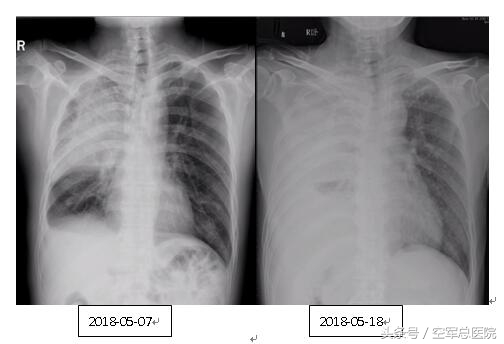

患者影像学的快速变化

穿刺过程险象环生。宋主任发现患者影像学病程进展迅速,不仅右肺完全实变,左肺也出现了多发病灶,且患者有明显缺氧症状,血气分析提示I型呼吸衰竭,穿刺过程中若发生气胸、出血等并发症,会导致病情恶化,有危及生命的风险。为此,刘一与宋云龙两位主任在充分讨论后,组织科室做好各项应急预案,并再次与家属进行详细沟通。